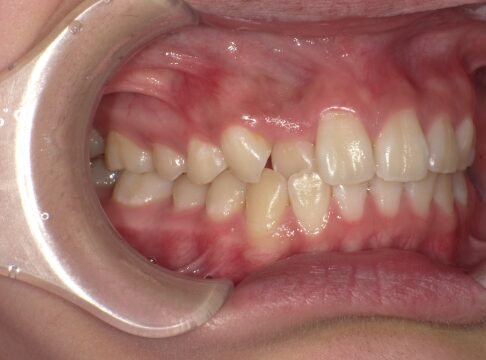

クロスバイト

治療前

ガタガタを主訴に当院を受診され、右上2番にクロスバイトを認めました。IPRを使用してマウスピース型矯正装置(インビザライン)を使用し改善を行いました。